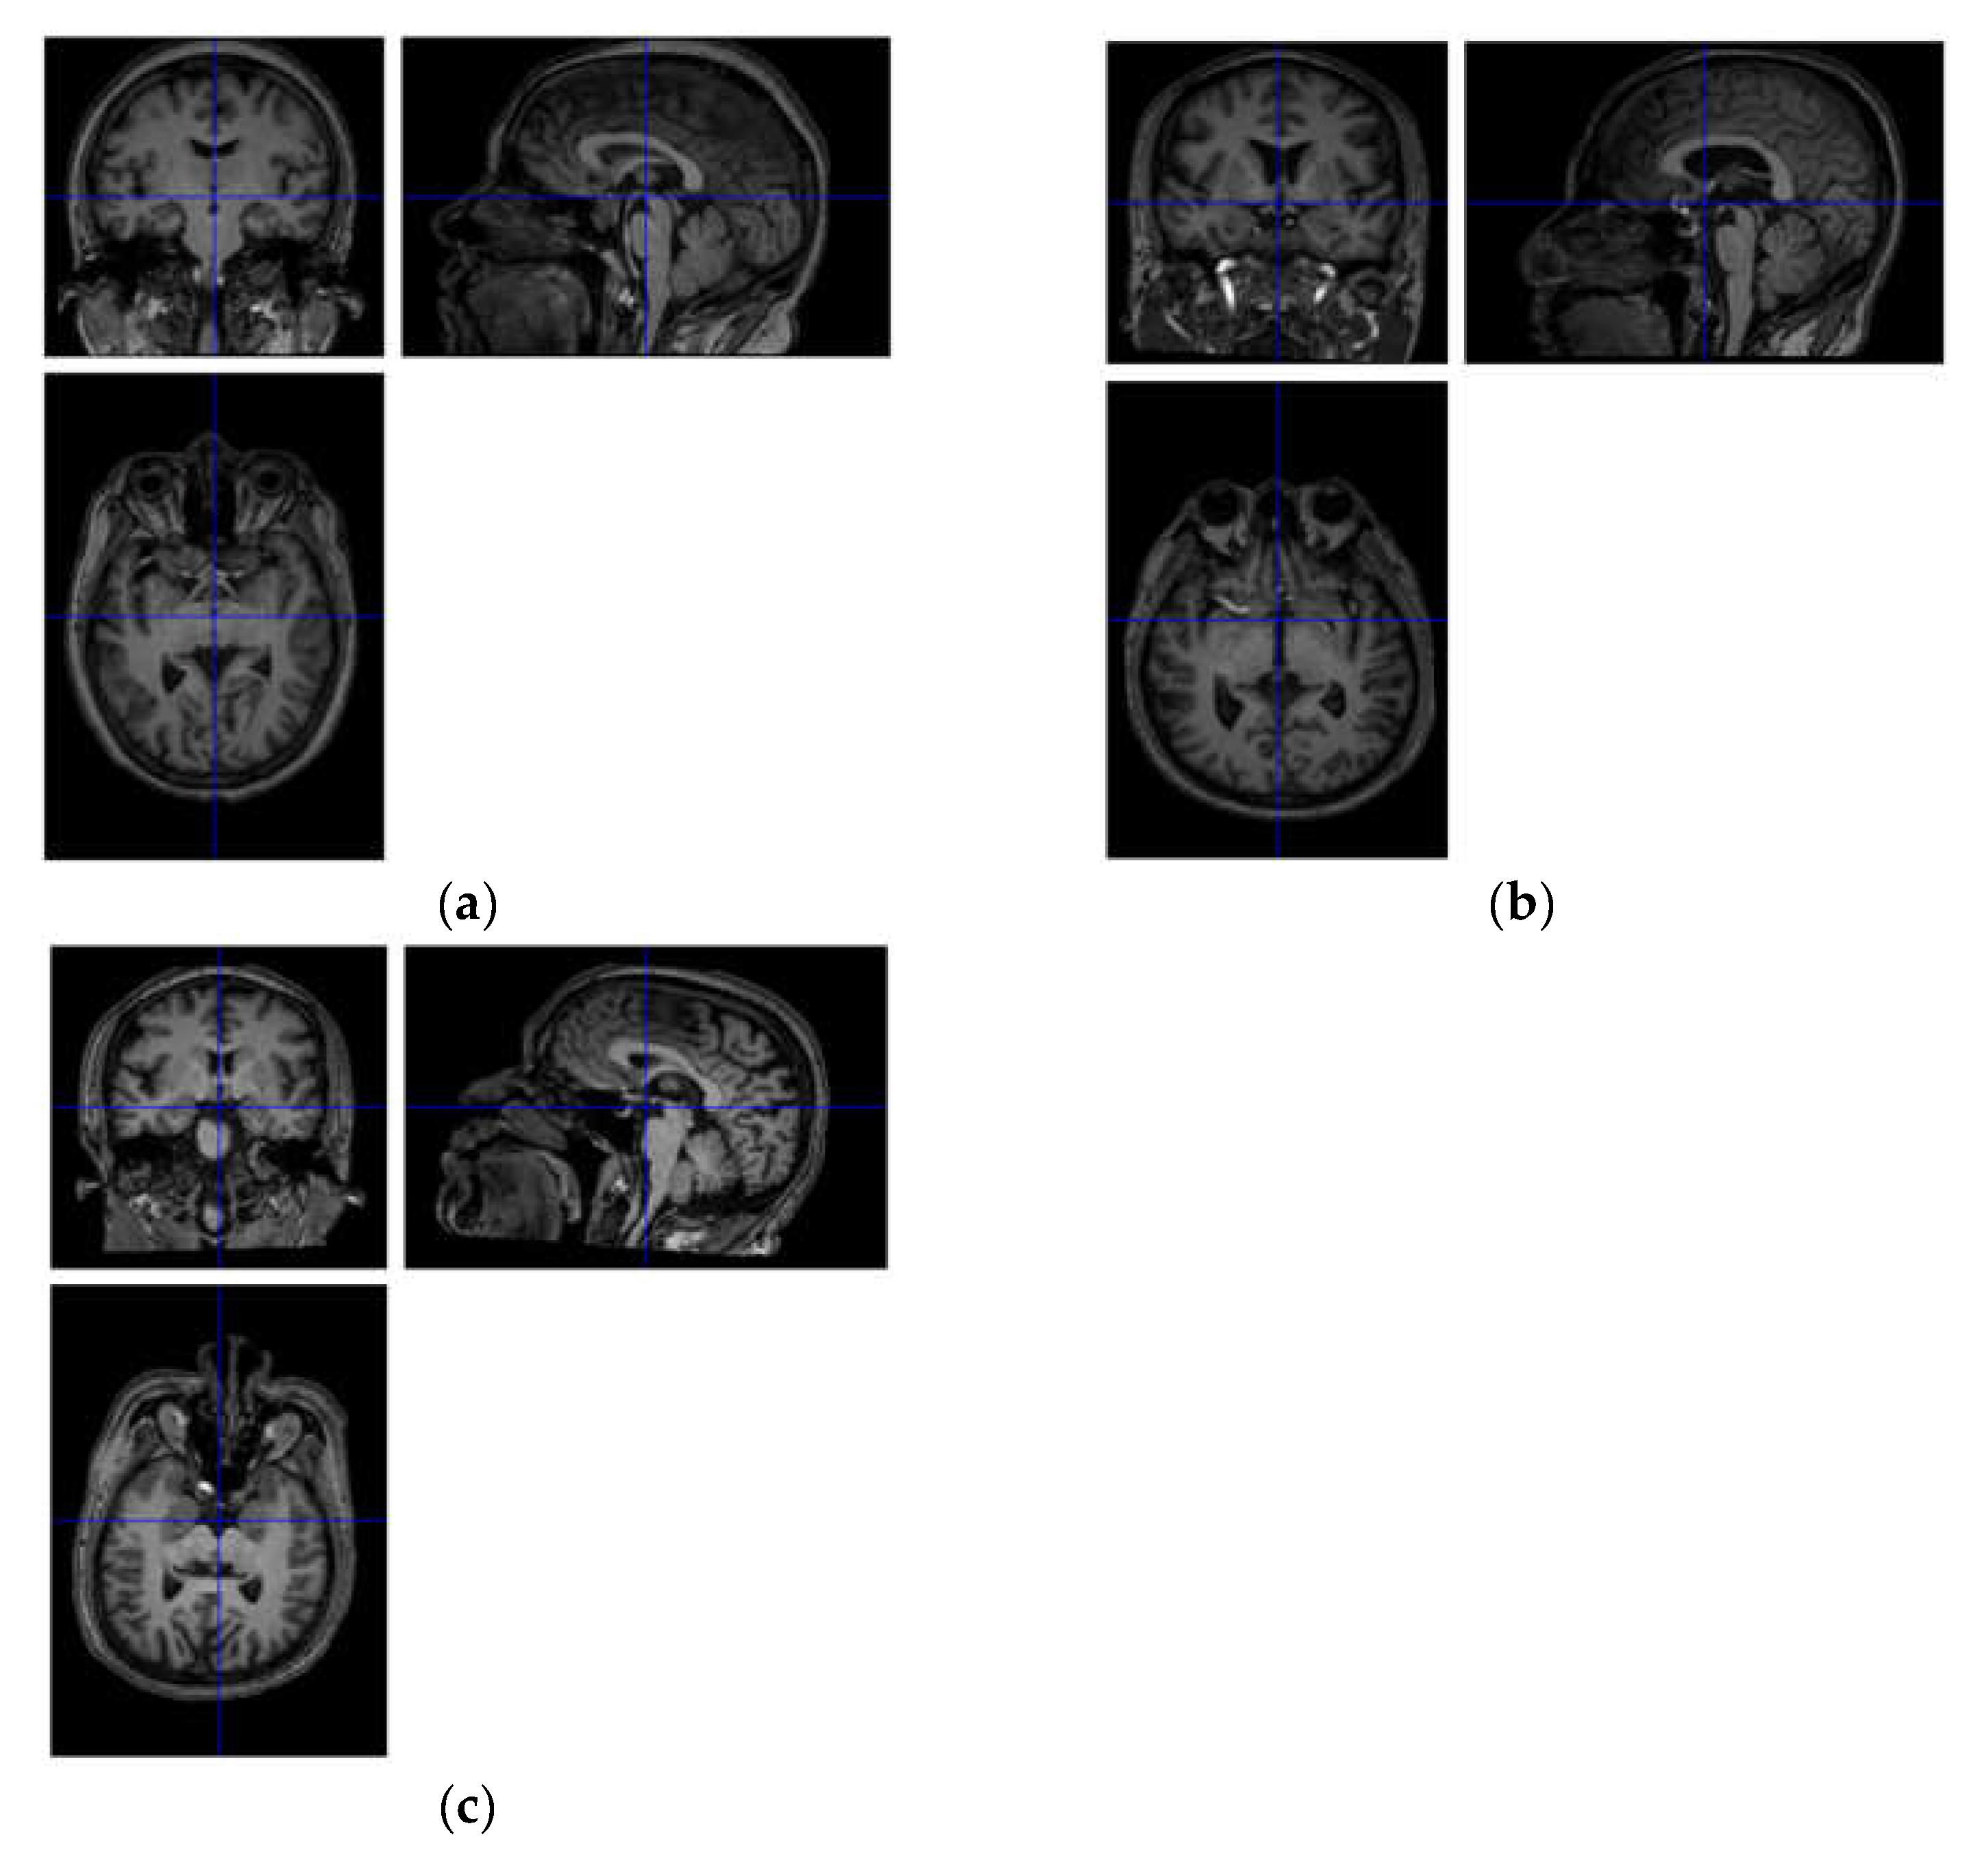

2.2. Structure Magnetic Resonance Imaging Data Acquisition and Preprocessing

2.3. Functional Magnetic Resonance Imaging Data Acquisition and Preprocessing